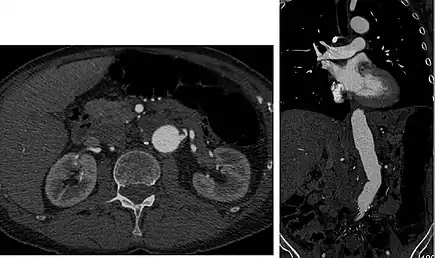

Early arterial phase (CT angiography)

CT angiography (CTA) is highly effective for evaluation of the arterial system, and has largely replaced conventional angiography due to the lower risk profile and ability to survey the entire abdomen. Images are acquired after a rapid bolus of intravenous contrast material (3-7 cc/s) during the arterial phase (15-35 seconds after injection) when the concentration of contrast material in the arterial system is high (figures 3). Images are usually acquired using narrow collimation (<1 mm) and can be retrospectively reconstructed using dedicated 3-dimensional workstations and software. CTA is commonly used in the head and chest in the evaluation of pulmonary emboli, aneurysms, vascular malformations, dissection, bleeding and ischemia. Indications for early arterial phase imaging include: evaluation of aneurysms or dissections (cerebral, aortic, etc.), hepatic, splanchnic or renal arterial anatomy, and arterial imaging in liver or kidney transplantation. Single phase arterial imaging is often used in the evaluation of trauma patients either a complete chest/abdomen/pelvis examination with arterial phase imaging of the chest and portal venous phase imaging of the abdomen/pelvis or just a portal venous phase of abdomen and pelvis depending on the mechanism and severity of the trauma. CTA is also commonly performed in the abdomen and pelvis for evaluating vascular malformations and in the evaluation of bleeding. Mesenteric ischemia can also be evaluated using CT angiography. CTA of the abdomen and pelvis is often performed in combination with a CTA for evaluating the extremity vasculature.

FIGURE 7. Selected images from a renal mass specific protocol CT. Corticomedullary phase (axial 7a) demonstrates peripheral enhancement of the renal cortex with minimal opacification of the renal medulla. There is a large renal cell carcinoma in the left kidney (right in image) which can be differentiated from the normal renal parenchyma by the heterogeneous and differential enhancement. The renal artery and vein are opacified in this phase as well. The collecting system is not opacified (coronal reformat 7b). In the parenchymal phase, the renal cortex and the medulla are enhancing. The renal cell carcinoma in the left kidney is not as well defined when compared to the corticomedullary phase images, but is actually slightly more conspicuous. There is some contrast noted within the collecting system during this phase (7c).